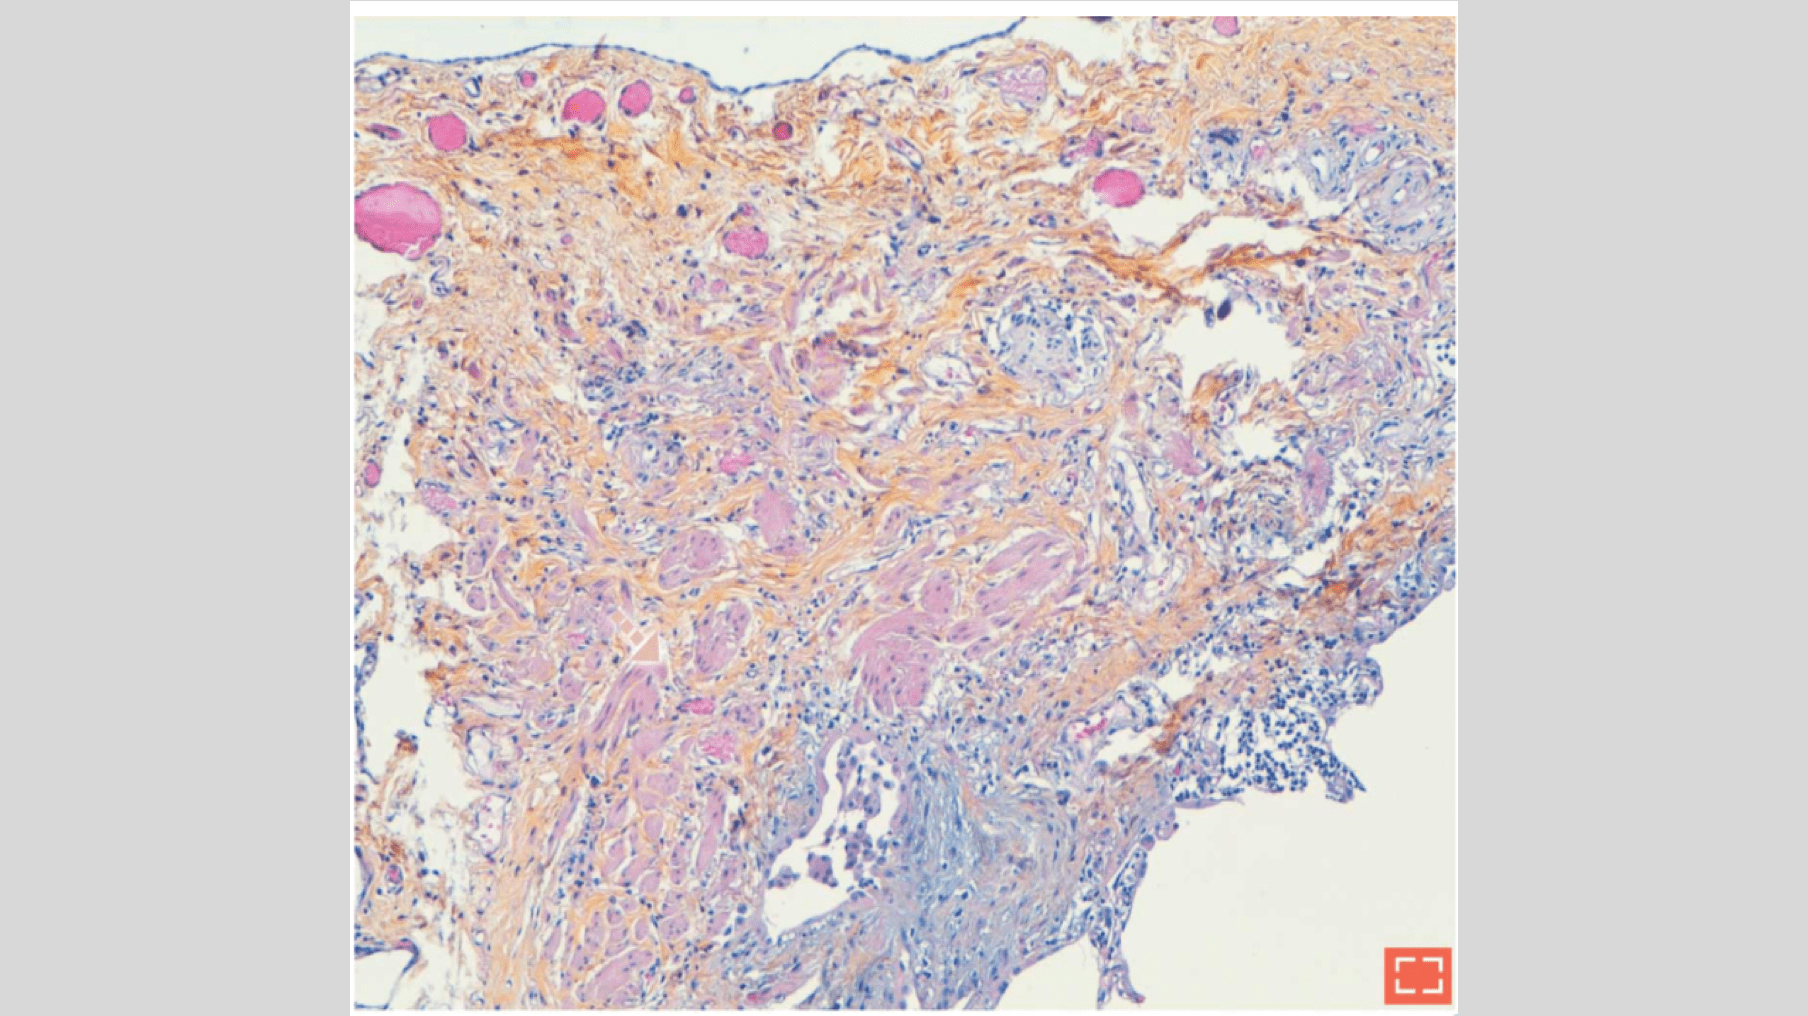

Smooth muscle hyperplasia (II)

• Hyperplastic smooth muscle bundles within subpleural fibrosis

Smooth muscle hyperplasia